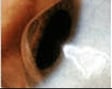

おもにレンズの汚れが原因で、上まぶたの裏側(=結膜)にブツブツができるアレルギー性の眼障害。かゆみや目ヤニが増え、レンズが上の方にずれやすくなります。ソフトコンタクトレンズやガス透過性ハードコンタクトレンズを使用している人に多くみられ、最近は増加傾向にあります。「アレルギー性結膜炎」などとの区別が必要です。